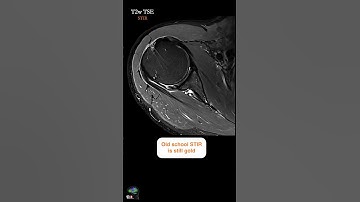

MRI – SCAPULA w/DEEP RESOLVE